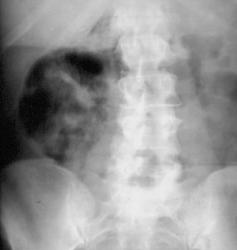

Вот снимок, представленный, как "Эмфизематозный пиелонефрит".

Знаменитый снимок, гуляет по всему инету. Как уверяют авторы  диагноз ставится по одному снимку.

Легче сказать сказать "чем это не может быть". И если это не 100 % "лажа" (компьютерные наложения), то единственное, что можно предположить - возможность наличия опухоли "эмбриональных зачатков". Остальное, как то брюшная беременность, с гибелью плода, наличие газа в забрюшинном пространстве (с одной стороны) исключаются. Смещение кишечных петель влево может свидетельствовать только об объёмном процессе.

Эта не "лажа" , а банальный

Эта не "лажа" , а банальный обзорный снимок органов брюшной полости.  Но если  раскрыть все карты Вы сильно разочаруетесь. т.к. все скиалогические эффекты тут объяснимы.

Эмфизематозный пиелонефрит.

Дело было так. Наш  хирург

Дело было так. Наш  хирург распечатал с инета данный снимок и принес его не планерку, со словами "что это". Снимок висел на сайте для абдоминальных хирургов, условие было такое: снимок весит 2 месяца потом раскрывают карты. версиий накопилось около сотни. Версия наших хирургов панкреанекроз,  безоар толстой кишки. Рентгенологов эмфизематозный пиелонефрит и кишечный свищь в забрюшинку.

То что это почка бросилось

То что это почка бросилось сразу. Обратите внимание на форму,положениеи самое главное для меня ось.  Недумаю что безоар может так четко имитировать форму и положение почки.

Весьма интересно. Но если это

Весьма интересно. Но если это эмфизематозный пиелонефрит, и именно пиелонефрит, то по идее должен был-бы газ хоть как-то дифференцироваться в полой системе почки, и позможно в лоханочно-мочеточниковом сегменте.

Если принять сказанное " на

Если принять сказанное " на веру", то газ, окружающий "почку" находится не в забрюшинном пространстве, а под капсулой почки, тогда непонятно, чем вызвана такая неоднородная структура тени почки и что это за "хвост просветления" направляющийся кверху?

Если это почка, как считаете

Если это почка, как считаете Вы, то каких она должна быть размеров - размеры не нормально большие и все газосодержащие структуры - петли кишечника дифференцируются слева, следовательно они смещены. Я не думаю, что орган находящийся в забрюшинном пространстве, даже таких размеров, хотя в медицине все возможно, так бы оттеснил кишечные структуры. А не было-ли авторами этого случая указано в каком положении был сделан снимок - стоя или лёжа. Не визуализируется и контур м. псоас, на мой взгляд она бедная прижата и зажата к позвоночнику. Вообще сам снимок весьма странный, так как он не внушает доверия, так как это не снимок почек и мочевыводящих путей, пусть обзорный, выполненный на кассете размером 30х40 см. с захватом всех необходимых компонентов. Это и не снимок брюшной полости, выполненный на кассете 35х35 см. или 30 х 40 см. с захватом куполов диафрагмы и "малого таза". Этот снимок произведен даже не с целью получить какую-либо диагностическую информацию, ибо если-бы эта цель была, то любой нормальный рентгенолог и даже  лаборант "соответствующего уровня" произвел-бы дополнительно правую боковую рентгенограмму. Меня сильно смущает и более интенсивное отображение газа справа, чем в петлях кишки слева. Что это за непонятная широкая тень просветления вдоль крыла подвздошной кости справа. А может быть это снимок "жмурика"? И что это за откол фрагмента костной ткани от медиального края крыла левой подвздошной кости.

Вот почему я и считаю данное изображение "лажей".

Здраствуйте! Жаль что опоздал на разбор! Случай на-интереснейший! Не настаиваю на утверждении, что смог бы сразу "раскусить" представленную патологию, но. Такое расположение газов весьма подозрительно на эмфизематозный пиелонефрит; и это хорошо описано в многих зарубежных руководствах по Урологии (Smith Urology) и Рентгенологии; и даже зайдя на такой известный инет ресурс как eMedicine, в разделе эмфизематозный пиелонефрит, первый опубликованный снимок будет весьма схож с представленным выше:

Согласен с Вами Валентин Львович, я о принципе: в нас когда-то вдалбливали-если в проекции почек на обзорной рентгенограмме брюшной полости в положении лёжа, мы видим ненормальное скопление газа-надо исключать эмфизематозный пиелонефрит. Мне запомнилось. )))

И вот, при детельном ознакомлении с материалом нашего коллеги, который представлен на "дружественном сайте", у меня возник невольный вопрос - "А не безоар - ли толстой кишки, мы обсуждали под маской "Эмфизематозного пиелонефрита", ибо некоторая аналогия прослеживается".

На мой взгляд, здесь картина типична для эмфизематозного пиелонефрита, а на дружественном сайте - болезнь Гиршпрунга